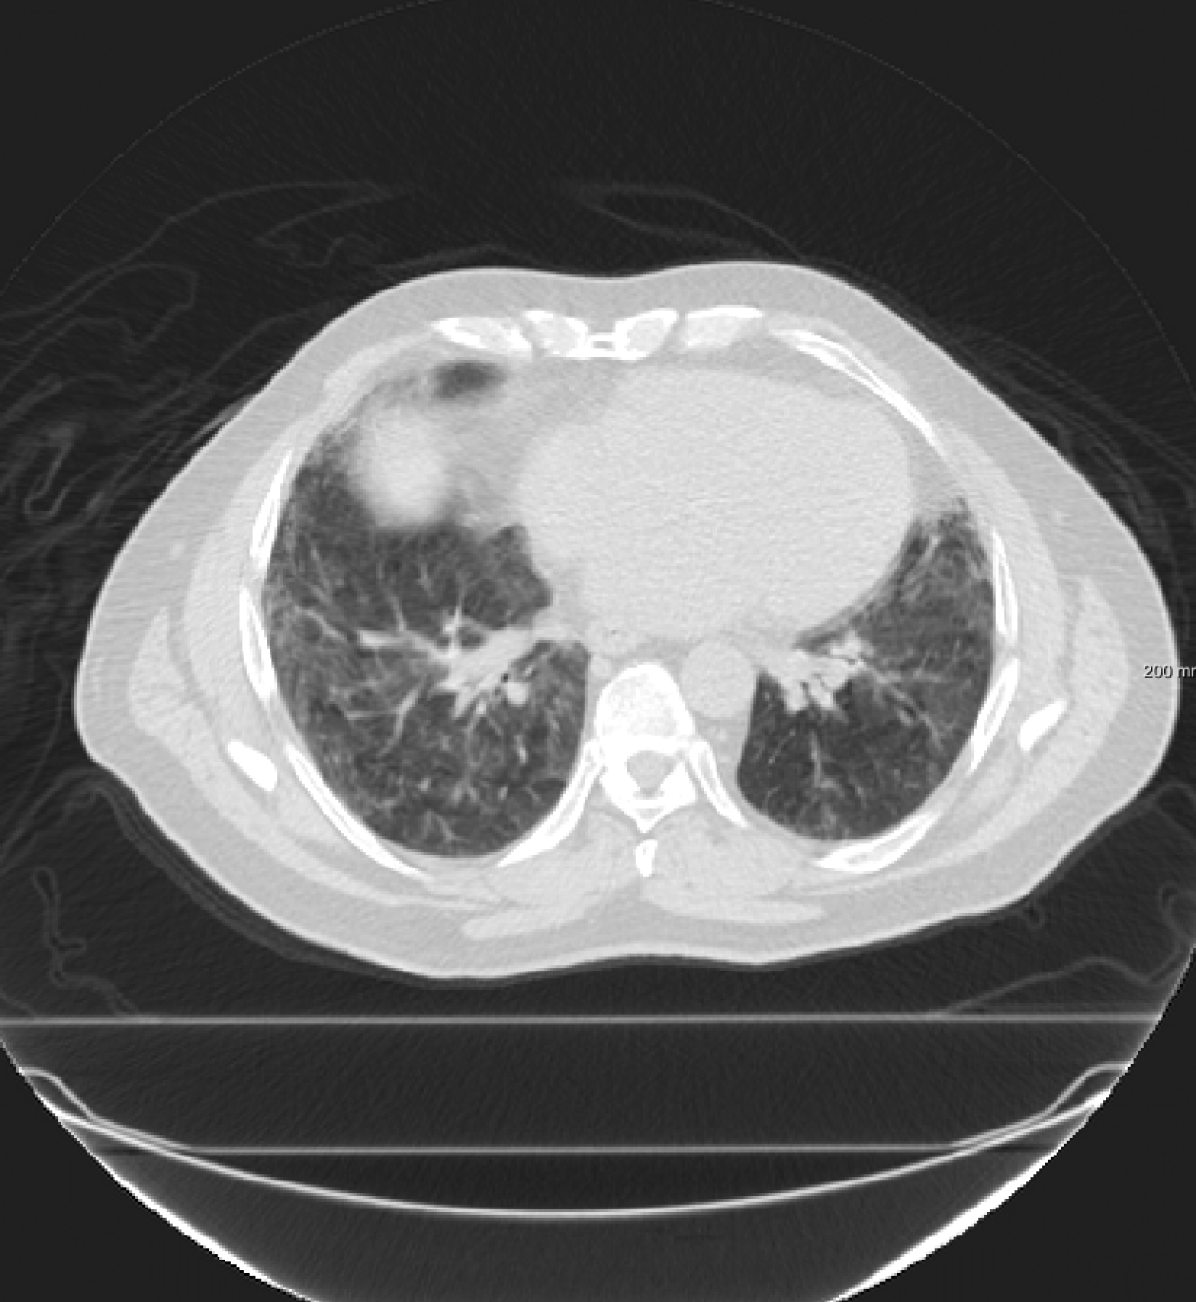

For the DIR-Lab-4DCT database, a comparison between RegNet and affine, B-spline (three resolutions), an advanced conventional registration method using sliding motion (Berendsen et al., 2014) and three other CNN-based methods (Eppenhof and Pluim, 2018; de Vos et al., 2019; Sentker et al., 2018) is available in Table IV. It can be seen that training with “S+M” improved performance slightly with respect to just “S”. Adding the respiratory motion category improved performance substantially, as these are inhale-exhale pairs; this is predominantly caused by the patients where the TRE after affine registration was still quite large. An example visualization is also available in Fig. 5(f), showing that adding the respiratory motion category can align images better in the diaphragm region. The advanced conventional registration method that leverages sliding motion (Berendsen et al., 2014) is still better than RegNet. Note that RegNet was not trained on the DIR-Lab-4DCT data, similar to Eppenhof and Pluim (2018); Sentker et al. (2018). However, de Vos et al. (2019) and Eppenhof and Pluim (2018)-DIR methods were trained on the same database but using cross-validation to report the results. Also note that the results reported in Sentker et al. (2018) are averaged over all phases of DIR-Lab-4DCT (T00 to T10), while the results of other CNN methods (including RegNet) are reported between the maximum inhale and maximum exhale phase (T00 and T50). These reported results are therefore likely somewhat better than the results for T00 and T50 only.